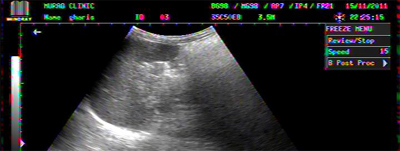

BILATERAL PLEURAL EFFUSION IN A 03 YEARS OLD BOY WITH DHF

BILATERAL PLEURAL EFFUSION COMPLETELY REABSORBED AFTER 3 WEEKS